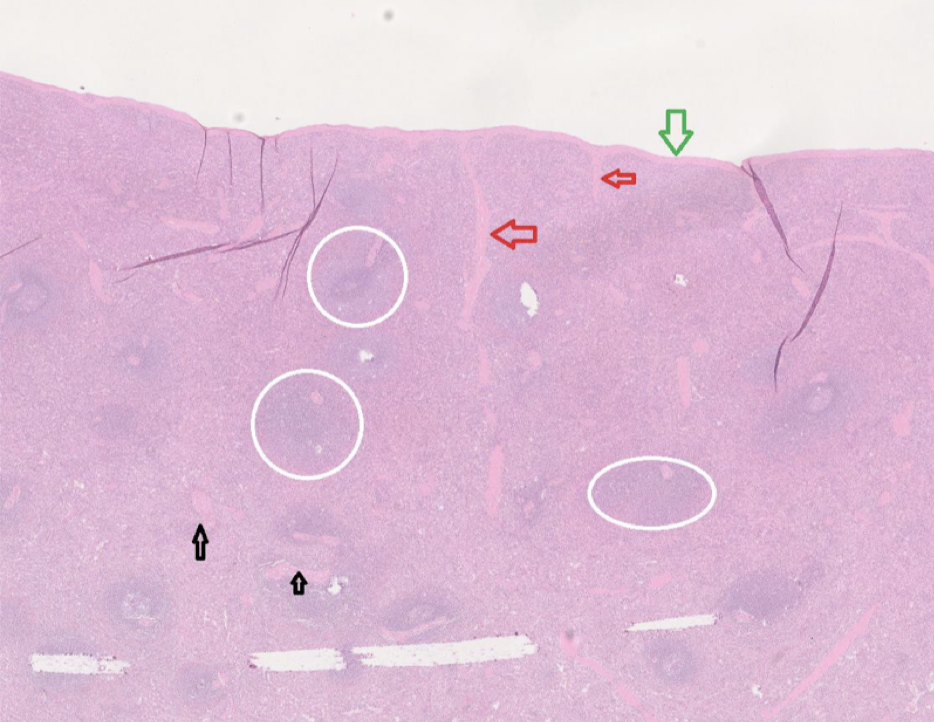

Vad är lyfnodens histologi?

Rött: Kärl.

Blått: efferent lymfkärl.

Svart: Sinus.

Cirkel: Primärfollikel.

Hexagon: Paracortex (T-cellszon).

Rektangel: Medulla.

Vad är mjältens histologi?

Grön: Fibrös kapsel.

Röd: Trabekler.

Vit ring: Vit pulpa.

Svart: Kärl